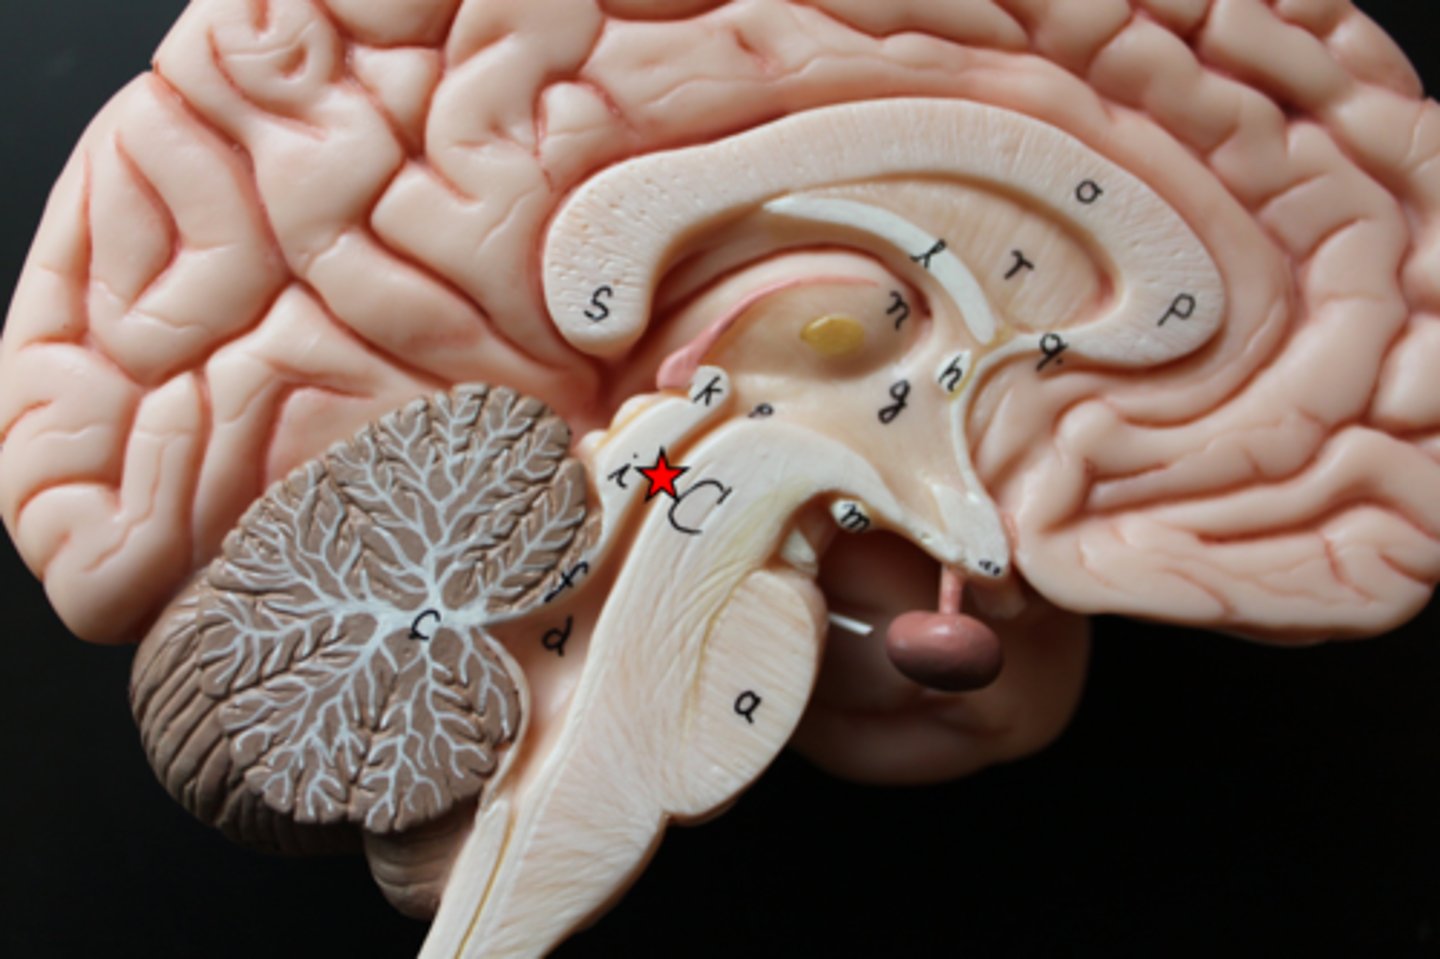

diencephalon

thalamus and hypothalamus

thalamus

relay station for all somatosensory information

intermediate mass

connection between the two thalami across the third ventricle, dumbbell shape

hypothalamus

brain region (many nuclei) in charge of maintaining homeostasis

pituitary gland

produces hormones

mammillary bodies

olfactory relay stations

epithalamus

region above midbrain that contains pineal gland

pineal gland

regulates sleep-wake cycles, secretes melatonin

cerebellum

balance, equilibrium, gross motor movement

vermis (cerebellum)

The tissue between the two cerebellar hemispheres

arbor vitae

"tree of life," white matter of cerebellum

cerebrum

cerebral cortex

outer region of the cerebrum, containing sheets of nerve cells; gray matter of the brain

corpus callosum

the large band of neural fibers connecting the two brain hemispheres and carrying messages between them

septum pellucidum

membrane that separates lateral ventricles

basal nuclei

internal masses of gray matter, smooth out motor movement

fornix